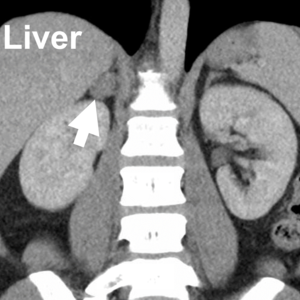

While adrenal vein sampling (AVS) is the gold standard for diagnosing subtypes of primary hyperaldosteronism (Conn’s syndrome), it is not always necessary for every patient. The decision to perform AVS depends on individual circumstances, and many patients may not need it at all. This is where consulting with an expert adrenal surgeon and team becomes crucial, as they can help determine whether...